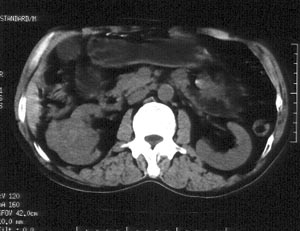

男性,56岁。右腰部不适2月。无血尿,无尿频尿急尿痛。b超提示:右肾下极占位。

ct平扫加增强扫描:右肾中下极肾盂外侧段实质见分叶状软组织密度肿块,截面大约56x45mm,向外突破肾包膜,向内突入肾盂,平扫密度略不均,ct值32-37hu。c+见病灶不均匀轻-中度强化,内有未强化坏死区。右侧肾周筋膜增厚,右肾内前方见肿大淋巴结。

ct诊断:右肾癌,ct表现见上述,伴同侧腹膜后淋巴结转移。

手术所见:右肾大小15x7cm,背侧有肿物突出肾包膜,大小7x4cm。行“右肾癌根治术”。

手术病理:

透明细胞癌(ⅰ-ⅱ级)